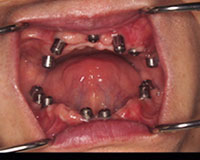

インプラント埋没後

全部の歯を抜き上下とも9本づつインプラントを埋入しました。

手術から7ヵ月後、一回目の仮歯の状態です。

歯茎の腫れも治まってきました。

まだ歯茎の状態は年々変化していきますので仮歯は数回作り変え、経過を観察後、最終的な固定的ブリッジが入ります。.